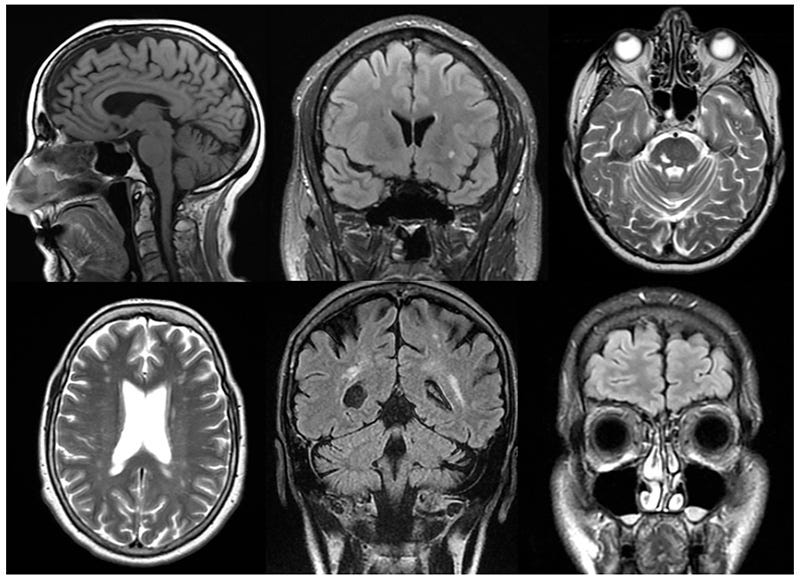

From left to right in the first row are cortical atrophy, white matter lesion, and vascular lesions and, in the second row, are lacunar lesion, vascular encephalopathy, and sinusitis.

First, let’s look at imaging results.

In SSPE, lesions of high signal intensity on T2-weighted images are the most common finding; they frequently involve the periventricular or subcortical white matter.

Thirty-four MRI studies of 26 patients with subacute sclerosing panencephalitis are reported. Lesions of high signal intensity on T2-weighted images are the most common finding; they frequently involve the periventricular or subcortical white matter. Lesions tend to start in the cortex-subcortical white matter and progress with periventricular white matter involvement and diffuse cerebral atrophy. Pial and parenchymal contrast enhancement, local mass effect of parenchymal lesions, and involvement of the splenic portion of the corpus callosum are not infrequent.

Note, again, that they occur in the periventricular and subcortical white matter. This is also the case in Long COVID.

White matter lesions: the Fazekas scale and the Standards for Reporting Vascular Changes on Neuroimaging (STRIVE) criteria are the most commonly used standards. White matter lesions are identified on FLAIR and T2-weighted images as bright (hyperintense) areas located in the periventricular or deep white matter.

Diffuse white matter hyperintensities are observed on FLAIR images. Subcortical infarcts, dilated perivascular spaces, or signs of microvascular disease may also be present. Cortical and subcortical atrophy is frequently associated with ventricular enlargement [17].

Brain Structural Abnormalities in Patients with Post-COVID-19 Headache